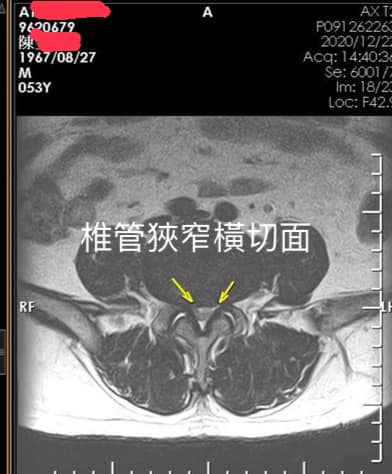

#安排MRI才知道椎管狹窄

🛑診斷:左側L3L4椎管狹窄

左側L4L5椎管狹窄

腰椎位於背部下方。椎管是腰椎內藏著脊髓及神經的管道,而椎管狹窄症是椎管內壁收窄,令脊髓和神經受壓而向外擴展 !腰椎管狹窄症一般會引致腿部抽筋、疼痛或麻痺,但亦可能導致背痛,雙腿失去知覺,甚至引起膀胱及腸功能問